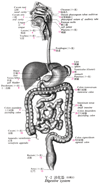

下行結腸Descending colon(Colon descendens)

下行結腸【かこうけっちょう】 Retroperitoneal segment of the colon extending along the left side of the body between the splenic flexure and sigmoid colon.(下行結腸は左結腸曲から下行し、左腸骨窩においてS状結腸へ移行する。長さ25~30cmで、左結腸曲からほぼ垂直に下行し、左結腸窩でS状結腸に移行する。下行結腸は、上行結腸に比べて、細く、前方には大網・小腸があり、後方には左腎臓の外側縁・腰方形筋・腸骨筋・大腰筋が接する。上行結腸と同様腸間膜を欠き後腹壁に固定されている。下行結腸に沿って結腸傍溝が走る。とくに外側の傍溝は下方で骨盤腔に連なり、上方では横隔結腸ヒダで境される。)